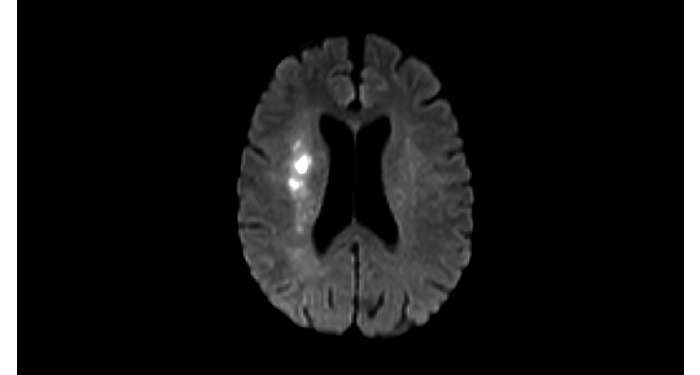

Hospital Eramse, Bélgica

Imágenes de la IRM de campos oscuros de un paciente con VIH con vasculitis cerebral

Las imágenes de campos oscuros ayudaron a sugerir el diagnóstico y elegir el tratamiento.